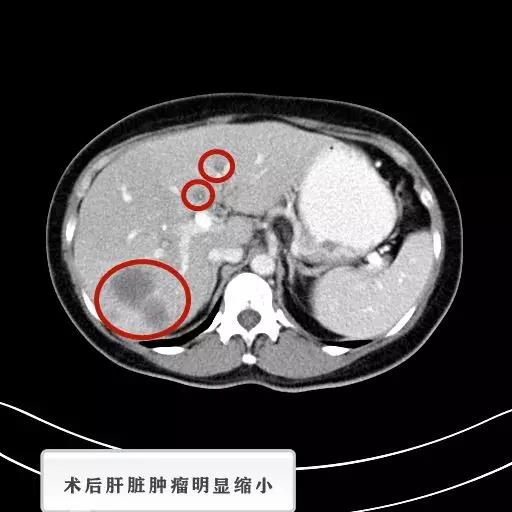

6月25号CT检查

在5月至8月期间,苏妮一共经历了4次介入治疗,每次治疗后苏妮表示自己很明显的感受到身体正在一点点变化,她很开心现在可以像以前一样享受到美食带来的快乐。每次的CT检查和肿瘤标记物都在以肉眼所见的速度下降。这次是她第6次介入治疗入院,在介入治疗做完后。陈医生拿着苏妮之前所做的检查结果和这次结果进行对比,嘴角上扬的说:“祝福你,苏女士,你可以不用再来医院做冷冻治疗了,你的肝脏上肿瘤基本都看不到,恭喜你,你可以回家了。”